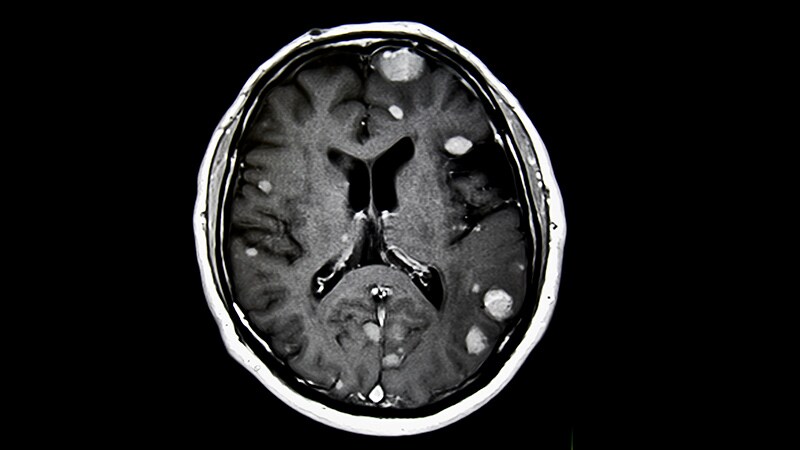

Brain Cancer

Biodegradable Brain Implant Delivers Life-Saving Cancer Meds

2021 Updates to the WHO Classification of Diffuse Gliomas

Tumor Treating Fields With Radiation for Glioblastoma